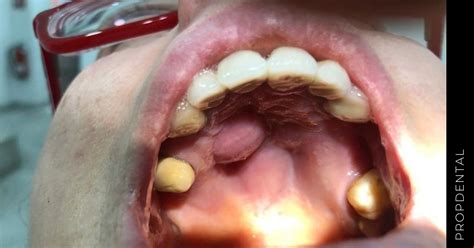

Caso Clínico: Absceso Palatino

Paciente de 39 años con seguimiento e historial clínico en Clínica Llobell, llama por teléfono indicando que tiene hinchado el paladar. Se aprecia un bulto en el paladar compatible con absceso. La paciente indica que es de aparición repentina y doloroso al tacto. Sus periodontogramas previos no indican pérdida periodontal de inserción. En clínica, se le pone anestesia local y se drena el bulto mediante incisión sulcular, seguidamente se limpia con medios mecánicos, ultrasonidos y curetas.